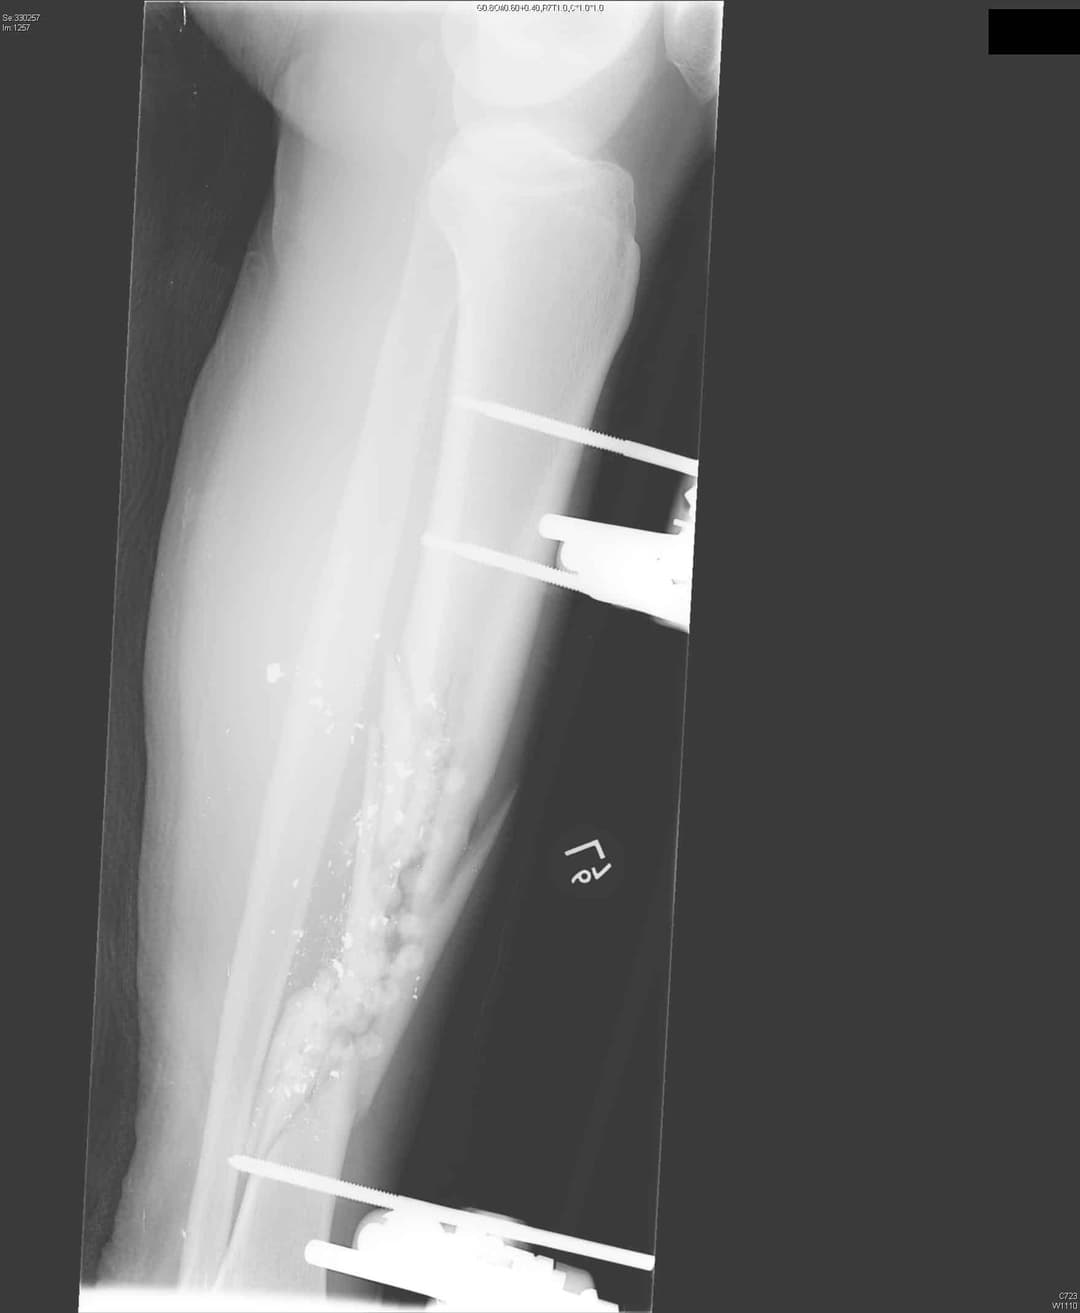

1. див. зобр. 8. Переднезадня рентгенограма встановлення зовнішнього фіксатора з приводу перелому великогомілкової кістки.

Зобр. 8

1. див. зобр. 9. Біпланарного контролю також можна досягти за допомогою напівштифтів, встановлених на передньомедіальній та передньолатеральний поверхні проксимального відділу великогомілкової кістки. Зверніть увагу на малогомілковий нерв збоку.

Зобр. 9